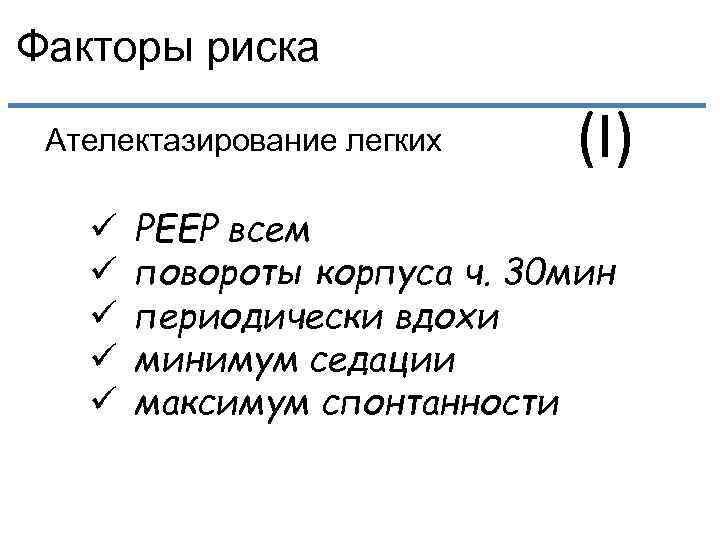

Факторы риска Ателектазирование легких ü ü ü (I) РЕЕР всем повороты корпуса ч. 30 мин периодически вдохи минимум седации максимум спонтанности

Факторы риска Ателектазирование легких ü ü ü (I) РЕЕР всем повороты корпуса ч. 30 мин периодически вдохи минимум седации максимум спонтанности